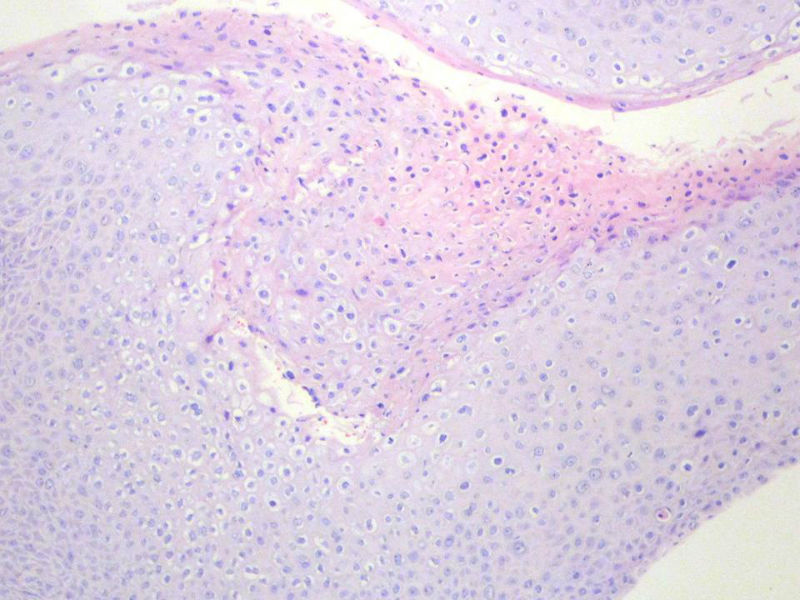

男,72岁,右耳听力下降两个月,检查右外耳道有黄豆大肿物,表面乳头状,手术切除。

请教:此例的组织像有恶变可能性吗?

乳头状瘤,有轻度异形,有恶变倾向

鳞状上皮乳头状瘤,未发现恶性变。